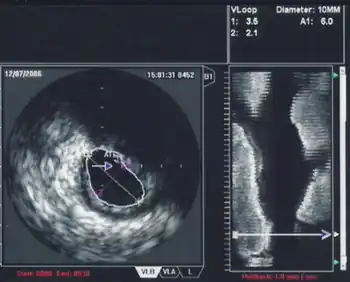

Intravascular ultrasound

An intravascular ultrasound image of the ostium of the left main coronary artery

Intravascular ultrasound, also known as a percutaneous echocardiogram is an imaging methodology using specially designed, long, thin, complex manufactured catheters attached to computerized ultrasound equipment to visualize the lumen and the interior wall of blood vessels.